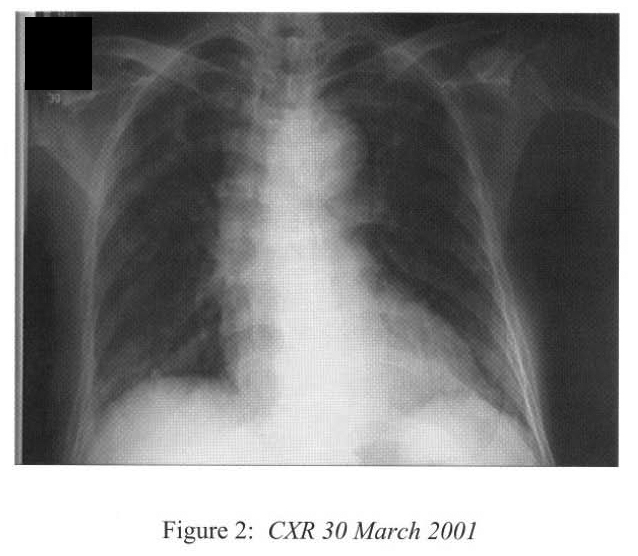

She developed swinging fever in the next few days and Vancomycin was added. However her general state continued to deteriorate with rapid radiological progression to adult respiratory distress syndrome (Figure 5), and cardiovascular collapse. She died 28 days after hospital admission.

Radiological features are also diverse and variable 15,16.On the chest radiograph, early signs include miliary shadows, diffuse reticular interstitial opacities, patchy alveolar opacities, segmental or lobar opacities. In the advanced stage, there can be extensive airspace shadows affecting both lungs, with occasional pleural or pericardial effusion. Without treatment, ARDS quickly evolves. Rarely, ARDS develops after antihelminthic treatment due to release of toxic breakdown products 17.On the abdominal radiograph, there can be thickened mucosal folds, segmental small bowel dilatation or perforation. Among all these variable radiological features, a characteristic pattern of Strongyloides hyperinfection has been described by the radiologists of Hong Kong, which consist of fleeting and rapidly changing CXR signs, predominant small bowel abnormality on AXR, and close temporal relationship of CXR & AXR signsl8. Detection of larvae in stool or other specimens is difficult (Table 1). Serological diagnosis19 is an attractive alternative but it is not available in Hong Kong.